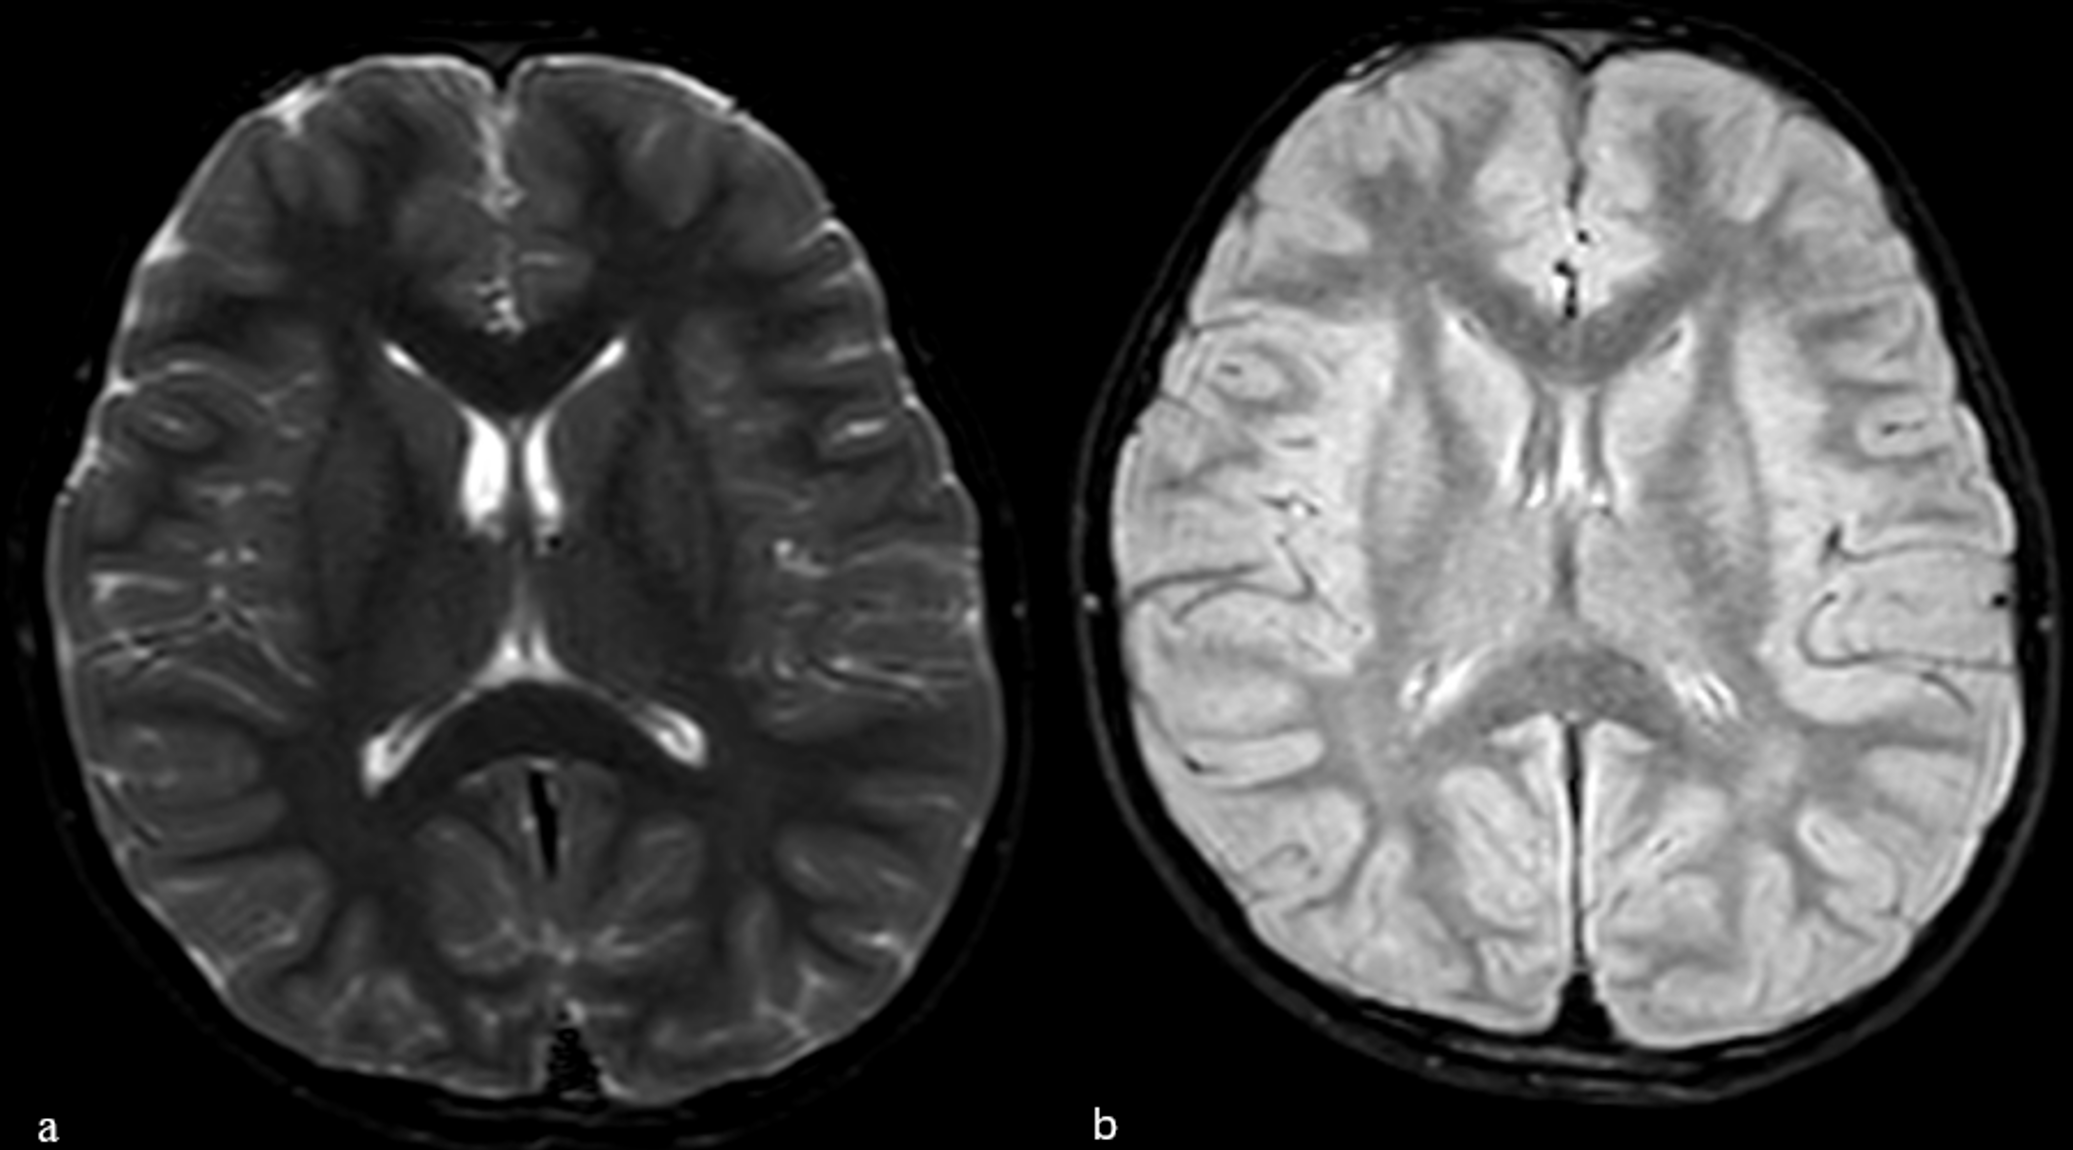

Given the severity of visual impairment and absence of other neurological signs, the patient underwent advanced imaging studies. Spinal and brain magnetic resonance imaging (MRI) was taken to differentiate demyelinating optic neuropathies (myelin oligodendrocyte glycoprotein antibody disease - MOGAD, neuromyelitis optica – NMO, and MS) in the differential diagnosis of optic neuropathy. Spinal MRI revealed diffuse intramedullary increased signal intensity in the cervical spinal cord at the C3–C6 levels on T2-weighted images; however, no associated cord edema was observed (Fig. 1). Furthermore, brain imaging demonstrated no evidence of demyelination in T2 and fluid-attenuated inversion recovery (FLAIR) sequences (Fig. 2).